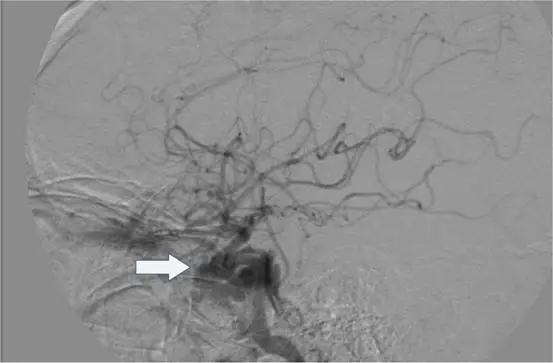

- 攝影視角:這是一張腦部數位減影血管攝影(DSA)的側位影像(Lateral view)。

- 血管特徵:影像中可見造影劑從頸部的一條主要粗大動脈向上灌注,並在顱底形成非常經典的「S型彎曲」,這個構造稱為頸動脈虹吸部(carotid siphon)。

- 分支供應:過了虹吸部後,血管主要向上及向後分支,顯影出**大腦前動脈(ACA)與大腦中動脈(MCA)**的分支網絡,這代表我們看到的是大腦前中部的血液供應(前循環)。

- 病灶標示:圖中白色箭頭所指處,位於內頸動脈的床突上段(supraclinoid segment),呈現一個囊狀的異常凸起,臨床上這是一個典型的內頸動脈瘤(如後交通動脈瘤 PCoA aneurysm 或眼動脈瘤 Ophthalmic aneurysm)。